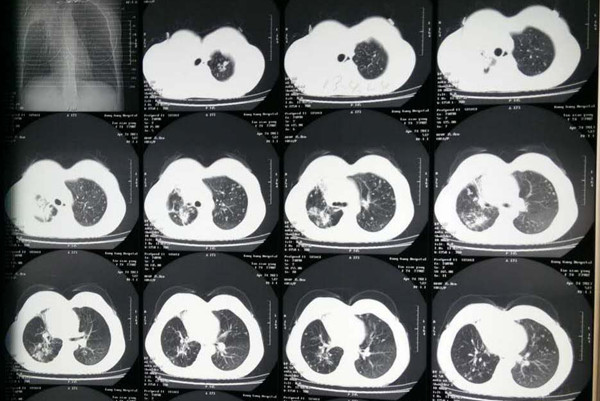

很多肺结核患者在被告知患上该病的时候,就非常困扰和焦虑,担心肺结核治不好怎么办,但其实只要规划的治疗,肺结核的治愈机会还是非常大的,下面我们就来看下如何规范化治疗肺结核?

专家强调肺结核规范治疗必须遵循“早期、规律、全程、联合、适量”主要原则。